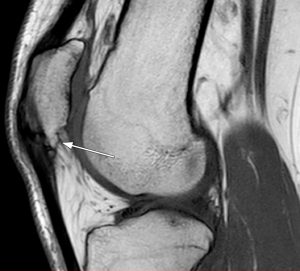

Diagnostisch wegweisend ist ein lokaler (Druck-)Schmerz am Ansatz des Ligamentum Patellae im Bereich des distalen Patellapols. Radiologisch können bei chronischen Verläufen oftmals knöcherne Ausziehungen am distalen Patellapol diagnostiziert werden. Im MRT zeigen sich bei chronischen Verläufen die typischen Befunde einer degenerativen Sehnenschädigung (siehe Abbildung 1).

Abb.1: Darstellung eines chronischen Patellaspitzensyndroms bei einem 30 Jahre alten Basketballspieler. Deutlich zu erkennen sind der große Patellaspitzenosteophyt sowie die ansatznahen degenerativen Veränderungen im Sehnenansatzbereich.